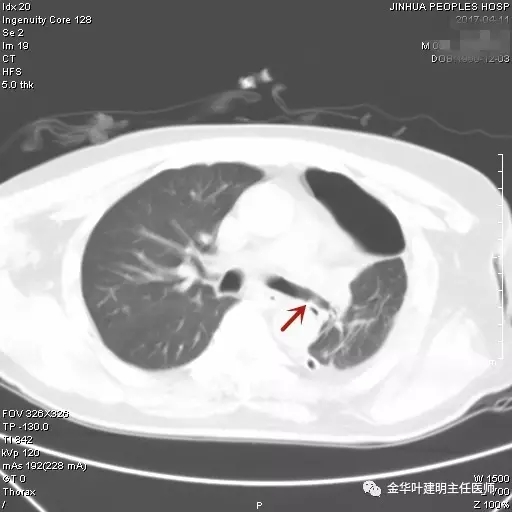

图三示:术后第9天胸部CT平扫见左主支气管与左肺下叶支气管吻合处通畅满意